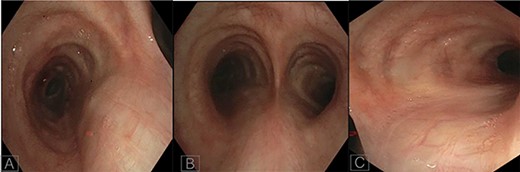

A 36-year-old female with past medical history of primary ciliary dyskinesia (PCD), chronic sinusitis and bronchiectasis with Pseudomonas Aeruginosa and Aspergillus colonization underwent bilateral lung transplantation. Based on the CT of the chest, both right and left main bronchi prior to lung transplantation were 47 mm in length, with a carinal bifurcation angle of ~55° (Fig. 1A). Prior to lung transplantation she had bi-lobed right and left lungs, with a right main bronchus which was as long as the left, which is a feature of situs ambiguous, i.e. left isomerism (bilateral left-sidedness). She had normal atrio-ventricular and ventriculo-arterial morphology though her cardiac apex was mildly shifted to the right (dextrocardia). Post transplantation, she was admitted as an outpatient for evaluation of declining lung function as detected on pulmonary function tests. She underwent repeat CT and bronchoscopy with transbronchial biopsies to evaluate for graft rejection. Interestingly, after transplantation her repeat CT (Fig. 1B) and surveillance bronchoscopy (Fig. 2A–C) revealed both right and left main bronchi that were 32 mm in length, with a normal tri-lobed right lung and a bi-lobed left lung. The right main bronchus was now at a right angle (90°) with the trachea. The composite bronchopulmonary situs was the result of isomeric recipient main bronchi (situs ambiguous) and normal donor lungs (situs solitus).

In our patient, the lengths of the right and left main bronchi prior to lung transplantation were 47 mm each, which was suggestive of left-sided isomerism. Notably, her post transplantation CT (Fig. 1B) and bronchoscopy (Fig. 2A–C) revealed both main bronchi to be of equal length (32 mm), which was longer than a normal right-sided bronchus (20 mm) yet shorter than a normal left-sided bronchus (50 mm). The right main bronchus was now at a right angle with the trachea and connected to a normal tri-lobed donor lung, while the left bronchus was anastomosed to a normal bi-lobed donor lung.

Bronchoscopy images of left main bronchus (A), carina (B) and right main bronchus post transplantation (C).